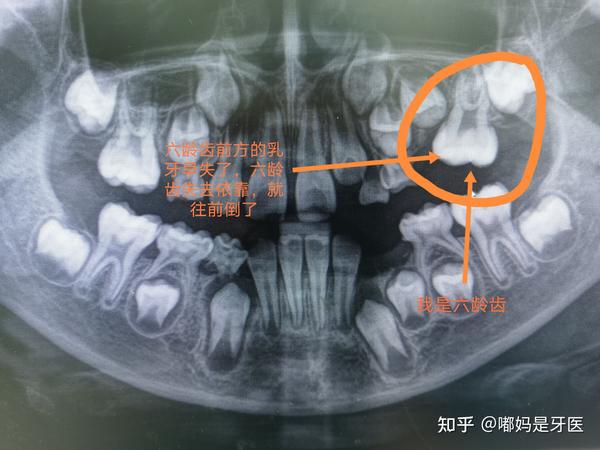

乳牙x光照,乳牙x光

乳牙有蛀牙,是否影响到下面的恒牙?

乳牙缺失后最重要的事,先检查要不要做缺隙保持器